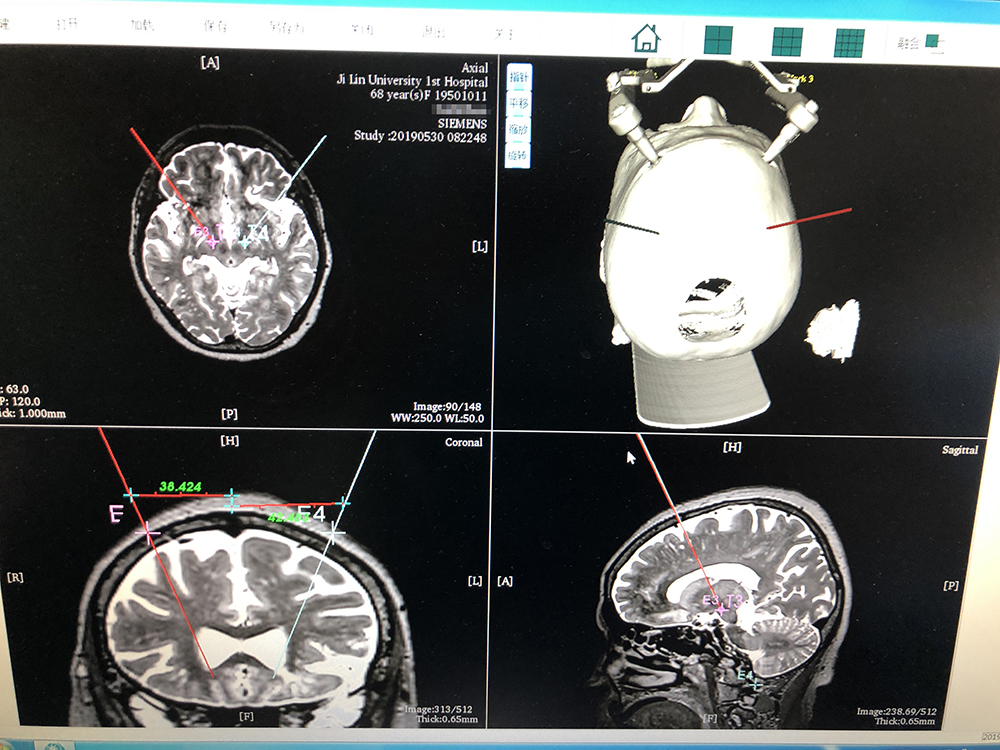

術(shù)前,邱吉慶教授借助“睿米”神經(jīng)外科手術(shù)機(jī)器人配套軟件,為患者制定雙側(cè) STN 核團(tuán)植入電極的手術(shù)路徑規(guī)劃。

借助“睿米”軟件制定手術(shù)規(guī)劃

手術(shù)規(guī)劃完成后,分別完成機(jī)械臂注冊(cè)和患者注冊(cè),系統(tǒng)顯示注冊(cè)精度分別達(dá)到0.07和0.16,符合 DBS 手術(shù)臨床的高精度要求。為進(jìn)一步確認(rèn),利用隨機(jī)驗(yàn)證點(diǎn)進(jìn)行精度驗(yàn)證,確認(rèn)誤差在1mm以?xún)?nèi)。

借助驗(yàn)證點(diǎn)驗(yàn)證定位精度在1mm以?xún)?nèi)